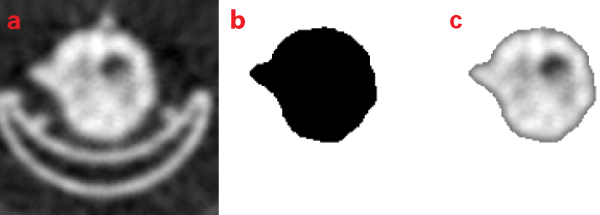

| Figure 1: Manual editing for removal of the bed from the PET transmission image. Image (a) is the original PET transmission image. Image (b) is the binary mask used to extract the region of interest. Image (c) is the extracted region used in the automatic image registration programs. The masking was also done to the MR image to remove any background noise and the fiducial markers for automated image registration. |